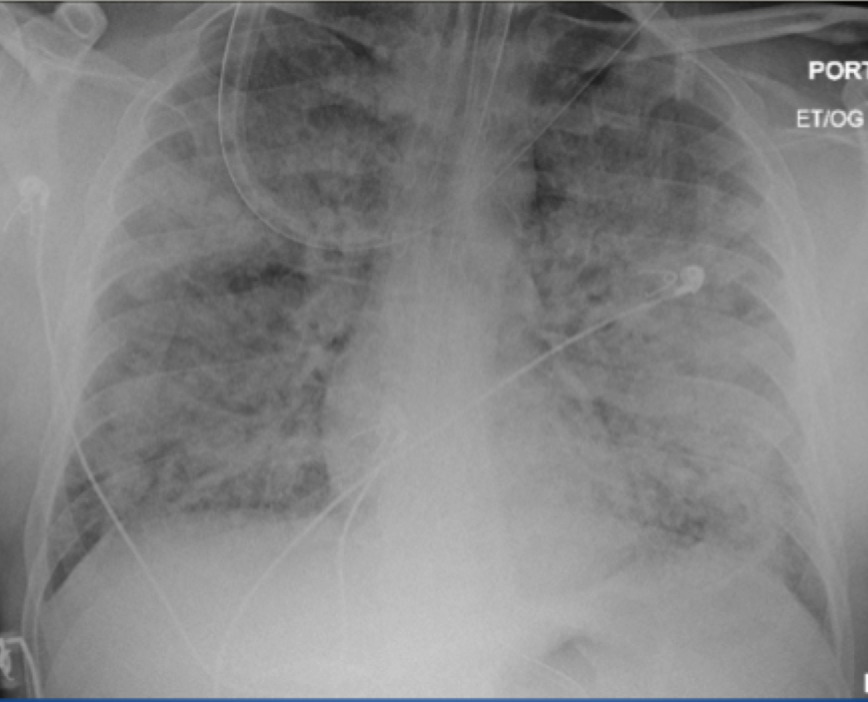

?

A

Acute respiratory distress syndrome

- normal heart

-no pleural effusion

-bilateral widespread pulmoonary inflitrates

-air bronchograms

11

Q

12